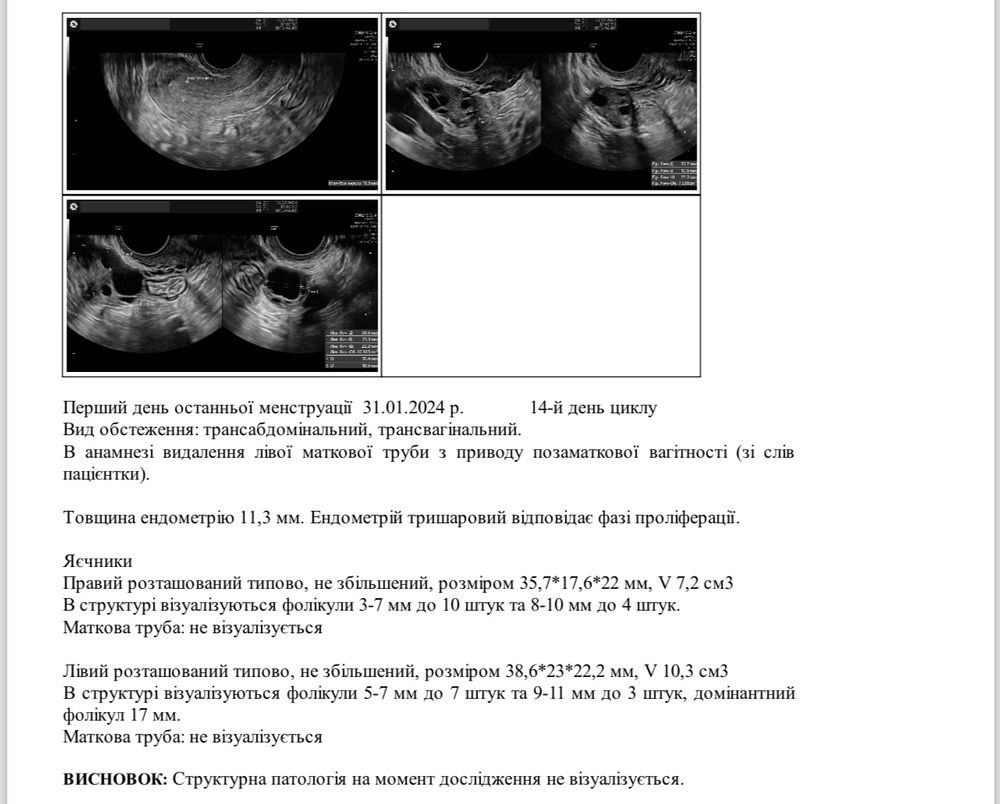

Девочки , скажите пожалуйста, есть ли шанс, что в правом яичнике тоже произойдет овуляция?😢У меня в левом доминантный фолликул, но там нет трубы😭 И может у вас было такое , что о произошла в яичнике ,где нет трубы, но б наступила ?Поделитесь пожалуйста 🙏